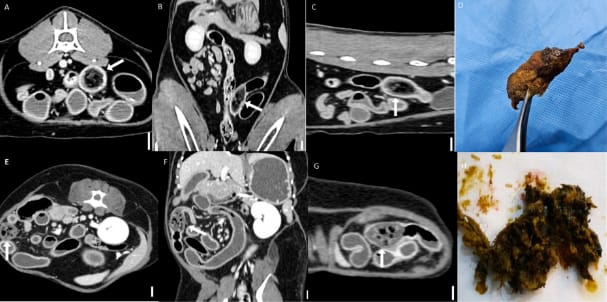

Representative CT images of bezoars (scale bar equals 1 cm). (A–C) Multiplanar CT images of a jejunal bezoar: (A) transverse, (B) dorsal, and (C) sagittal views. The bezoar (arrows) appears as an intraluminal mass with a mottled gas pattern. (D) The corresponding surgically removed bezoar was identified as a trichobezoar composed of hair. (E–G) Multiplanar CT images of another jejunal bezoar: (E) transverse, (F) dorsal, and (G) sagittal views. The bezoar (arrows) exhibits similar mottled gas appearance. (H) The corresponding foreign body was identified as a trichobezoar primarily composed of synthetic fibers, likely originating from toy fragments.